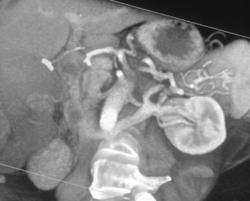

Renal Artery Aneurysm